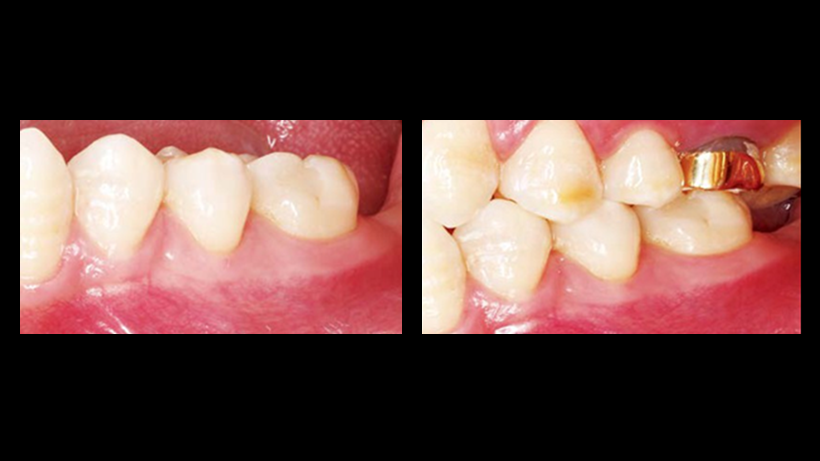

Clinical case: Immediate post-extraction insertion of implant & immediate loading

- Courtesy of Prof. Giuseppe Luongo, Italy -

AnyRidge, immediate loading, single implant, multicenter study, maxillary anterior, Prof. Giuseppe Luongo, single replacement

AnyRidge implant system